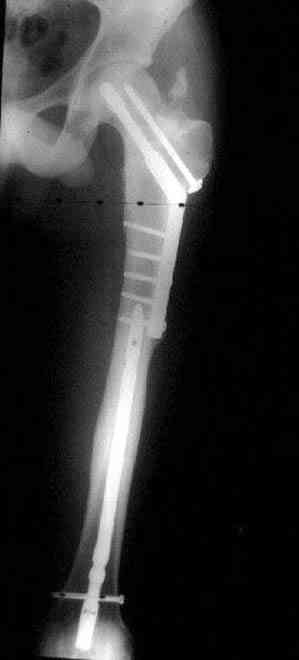

Вложение не в текстовом формате было извлечено…

Имя     : ipsilateral neck shaft postop.JPG

Тип     : image/jpeg

Размер  : 36845 байтов

Url     : http://weborto.net:8080/pipermail/ortho/attachments/20080114/94c631b9/attachment-0013.jpeg